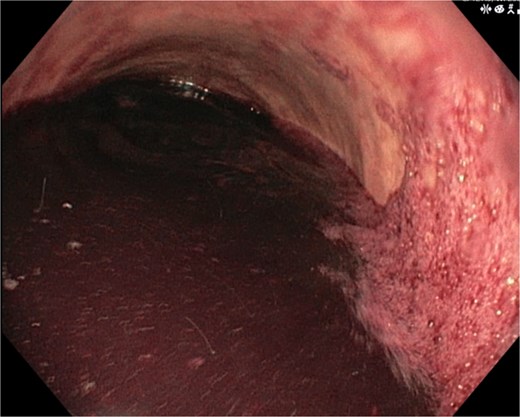

A 46-year-old male with a history of achalasia, for which he had undergone Heller myotomy with Nissen fundoplication in 2015, presented to the emergency department with a 2-day history of weakness and hematemesis. On admission, laboratory investigations revealed a significant drop in hemoglobin to 5 g/dl. Vital signs demonstrated tachycardia (122 beats per minute) and hypotension (70/50 mmHg), consistent with hemorrhagic shock. Initial management included aggressive resuscitation. Emergent gastroscopy was performed, which revealed the stomach filled with blood but failed to identify a clear bleeding source (Fig. 1). The patient remained hemodynamically unstable, necessitating transfusion of additional blood products. A computed tomography angiography was subsequently performed, revealing a markedly dilated, sigmoid-shaped esophagus, likely a sequela of end-stage achalasia. Furthermore, a contrast blush in the region of the distal esophagus, consistent with active ongoing bleeding (Fig. 2). An initial attempt was made to control the bleeding through angioembolization; however, this attempt was unsuccessful.

Demonstrates the gastroscopy findings, showing the stomach filled with blood.